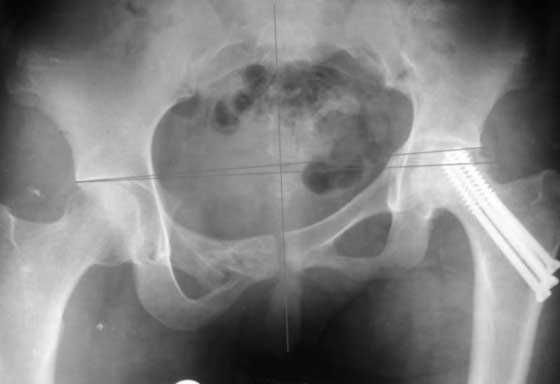

Привет, Макс. Не торопись, посмотри внимательно на истинную картину. Толстая стрелка указывает на нижний край смещенного кп сочленения.

Поэтому считаю, что Принять какое-либо решение без кт и дополнительных проекций неразумно.

разговоров нет, смещение значимое, какое оно было, такое и осталось. Будут проблемы и с сидением и с осанкой и т.д. Идеальным вариантом было бы, конечно, исправить деформацию, а потом запротезировать. Но... цена вопроса. сейчас деформация, судя по костной мозоли, стабильная, и таз несет основную свою функцию - опорную, явно КПС не болит. Превратить стабильную деформацию в нестабильную и потом ее исправить - задача непростая, но выполнимая. Оперативное лечение будет сложное, скорее всего многоэтапное и длительное. С определенными рисками, общехирургическими и специфическими, например несращение зоны остеотомий - нестабильный таз, ризидуальное смещение (в пределах 1 см вполне вероятно). Если считать, что на тазе укорочение см 3, остальные 5. все-таки сгибательно-приводящая контрактура. На протезе от контрактуры можно избавиться, да и см 2 удлинить за счет опила, головки. В такой ситуации решение должна принять пациентка и оно должно быть действительно информированным.